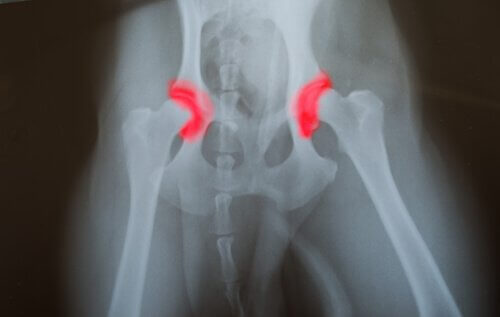

Hofte- eller albuedysplasi er en arvelig sygdom, som går fra generation til generation. Det er forårsaget af knoglerne, der danner et led – enten ved hoften eller albuen – som ikke er placeret eller justeret korrekt. Dette får dem til at gnide mod hinanden og lave forkerte bevægelser.

Dette forårsager et fremskyndet slid, hvilket forårsager andre problemer, som kan føre til malfunktion af ledene. Problemet med denne sygdom er, at den er stille.

Det betyder, at problemet kan have eksisteret i lang tid, endda siden fødslen, men dyret vil ikke føle nogen smerte, indtil de senere stadier i livet. Du vil bemærke det, fordi dit kæledyr vil gå fra at spise og hoppe til næsten ikke at være i stand til at bevæge sig overhovedet.